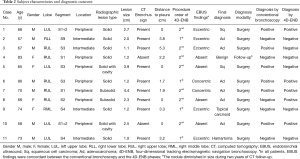

A total of eleven patients were enrolled between October 2013 and August 2017. The original target was 20 patients over 2 years; slow accrual prompted the decision to close the study before reaching this sample size goal. The patient characteristics and lesion information are summarized in Table 1. The details of each patient and diagnostic outcomes are listed in Table 2. There were seven male and four female patients with a median age of 67 years (range, 57–90 years). The mean size of pulmonary nodules on CT was 2.1 cm (median, 2.0 cm; range, 1.0–4.4 cm). Nine pulmonary nodules (82%) had a positive CT bronchus sign. Seven pulmonary nodules (64%) were located in the peripheral third lung field. The mean pleural surface-to-pulmonary nodule distance was 1.9 cm (median, 1.9cm; range, 0-5.3 cm). Representative CT images of the pulmonary nodules are shown in Figure 2. Seven cases underwent conventional bronchoscopy as the first procedure. Biopsy tools used for each case are shown in Table S1. Ten out of eleven patients underwent surgery for diagnosis and treatment. One patient (case #4) was surveilled by imaging alone, with a total of three CT scans over two years; the nodule was clinically diagnosed as benign due to diminishing size.

Full table

Full table